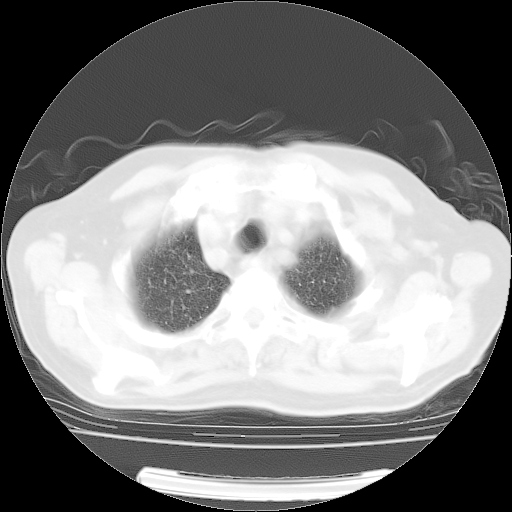

肺部CT平扫未见异常。

4月14日肺部CT